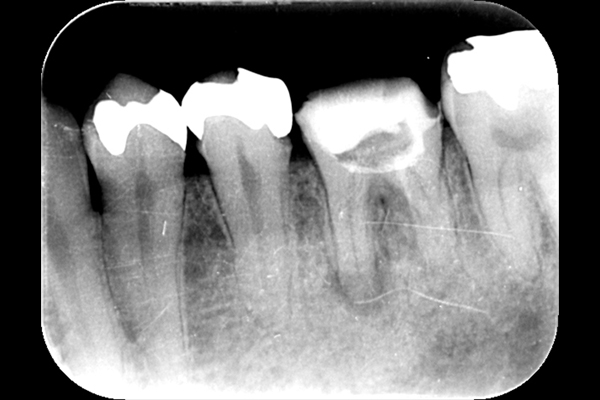

| 術後6ヶ月 | |

| 根の先の黒い影は消失しました。 | 術後6ヶ月のCT画像です。こちらでも、根の先に黒い影は見当たらないです。 |

このように外科的治療で病変部を切除することでしっかりと治癒させることが可能です。根の治療は細菌との戦いです。難しいですが、やりがいがあります。